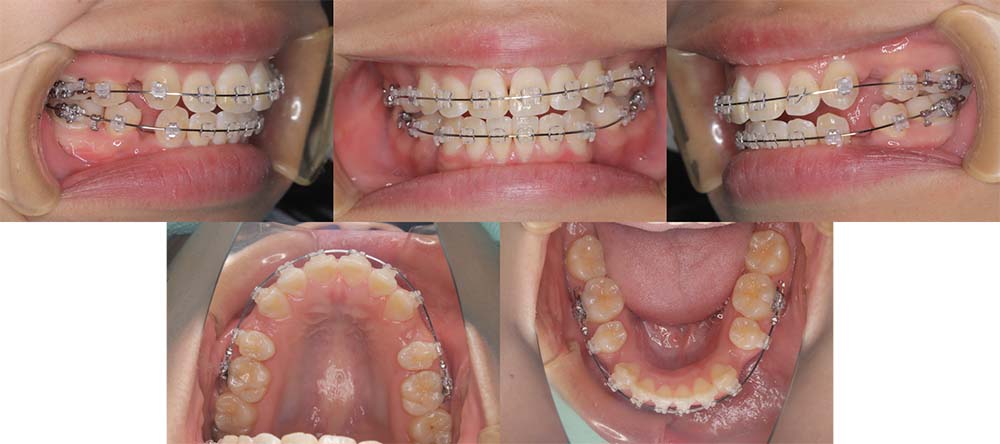

| 症例分類 | 顎変形症、叢生、開咬 |

| 診断名 | 上下軽度叢生を伴う骨格性開咬 |

| 主訴 | 前歯でものが噛み切れない、奥歯もあまり噛み合わない |

|---|---|

| 年齢 | 21歳9ヶ月 |

| 性別 | 女性 |

| 抜歯部位 | 上下左右の第一小臼歯(4本) |

| 使用装置 | 表側のワイヤー装置+外科矯正(手術を併用した治療) |

| 治療期間 | 1年8ヶ月 |

| 保定装置 | 固定式保定装置、取り外し式保定装置(8時間) |

| 費用 |

保険適応 [検査・診断等] 2万円程度 [装置装着] 5〜7万円程度 [調整料] 2,000〜7,000円程度/回 [手術前検査等] 2万円程度 [保定装置等] 4万円程度 合計18〜25万円程度 |

下顎の右側偏移があり、骨格的にも受け口だったため、上顎両側第一小臼歯を抜去して手術を併用して治療を行いました。術前は前歯が反対のかみ合わせになり、初診時より咬合、顔貌は一旦悪くなります。1年5ヶ月の術前矯正のあと手術を行いました。

手術後に使用が必要になるゴムの協力度が高く、手術後は7ヶ月の術後矯正で治療を終了することができました。

顎の歪みも下顎の前方感も改善することができました。